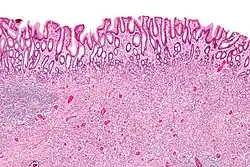

| Low magnification micrograph of an inflammatory fibroid polyp. H&E stain. | |